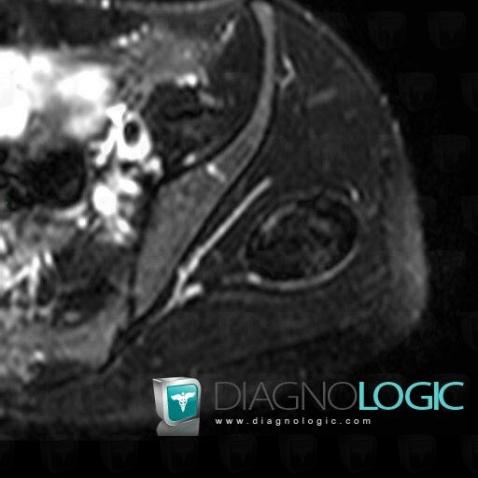

Hematoma, Pelvic Muscles, Other soft tissues/nerves - Pelvis, MRI

Here is the specific information in the key image above:

- Diagnosis Hematoma, Location(s) Other soft tissues/nerves - Pelvis, with gamuts Hypointense T2 WI soft tissue lesionPelvic Muscles, with gamuts Hypointense T2 WI soft tissue lesion